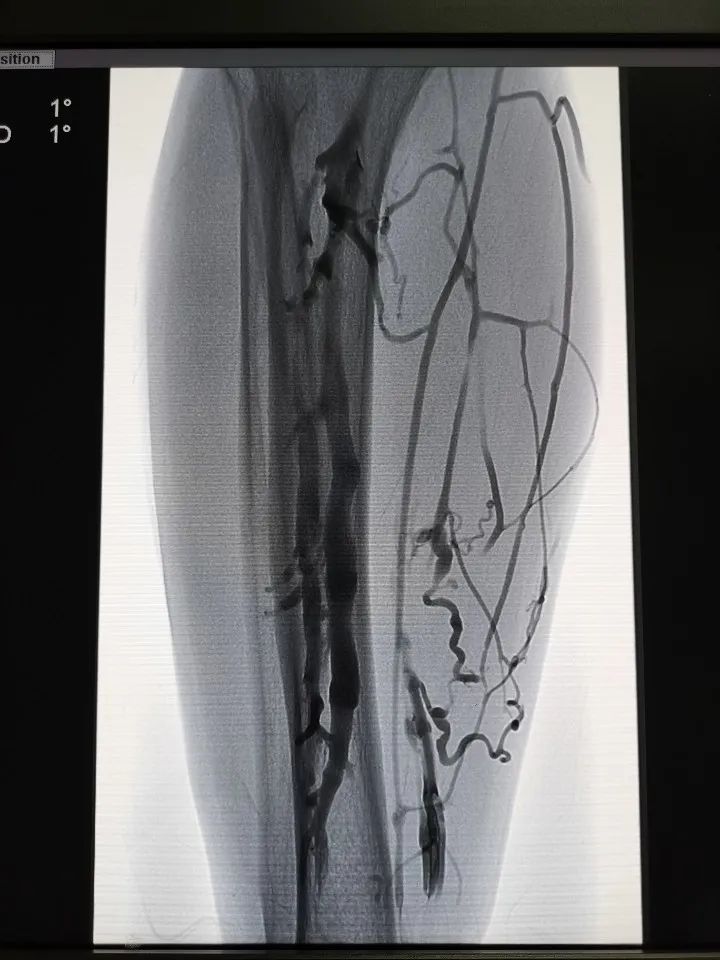

图为术前造影